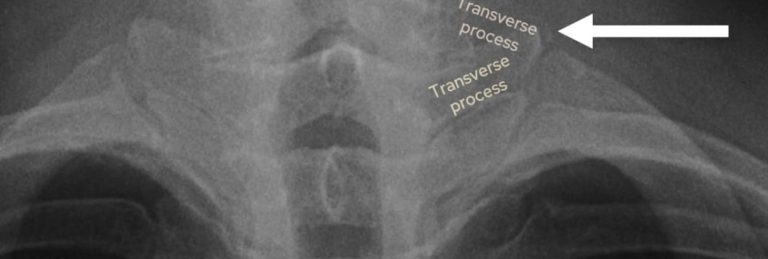

The first thing I check is rotation. Find the spinous processes and see how they line up with the inner ends of the clavicles. In a well-positioned film they should sit right in the middle. If the patient’s rotated, the mediastinum looks distorted, the heart size becomes unreliable, and one lung can look falsely more dense than the other just because it’s closer to the detector.

Assessing rotation: check to see the spinous processes are equidistant between the medial clavicles.